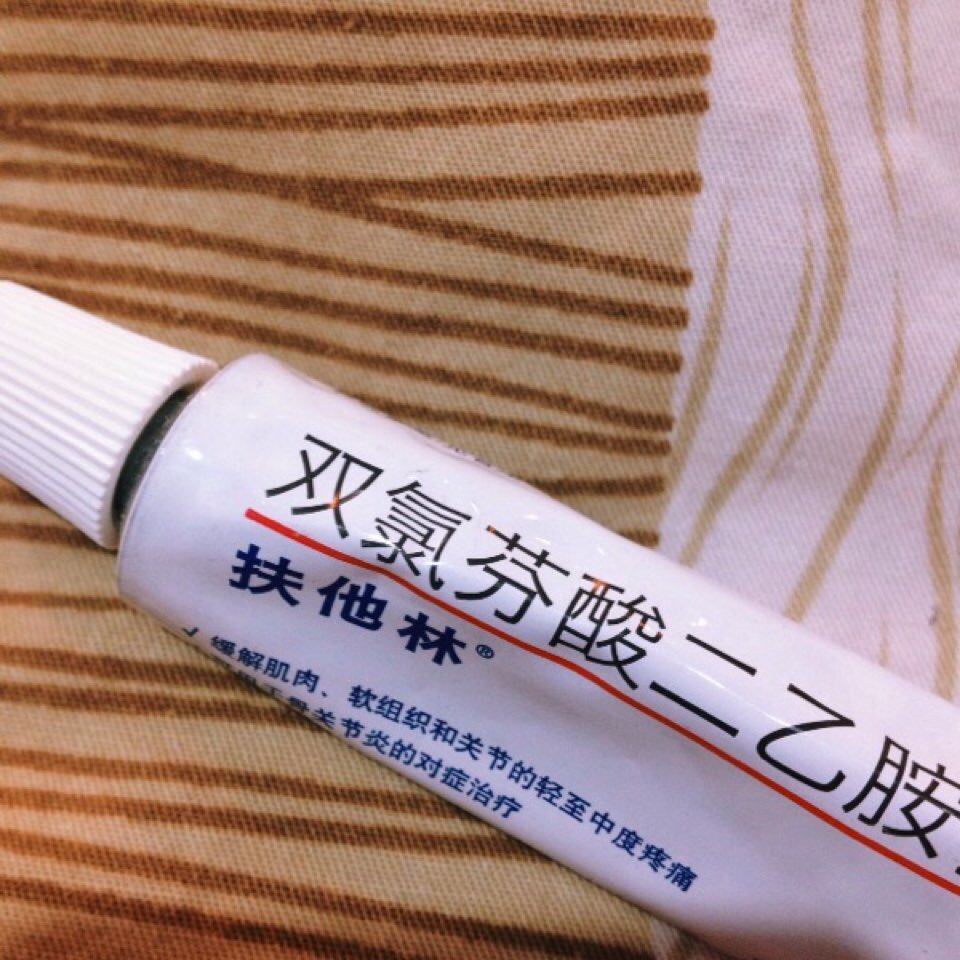

阶级会在一个人的身上留下最深刻的烙印。颈椎病、腰椎间盘突出、腕管综合征等,这一切都向我们表明,实时通讯的自动化社会改造了我们的身体。同样地,如果你的键盘用得足够得久,总有几个键帽会被敲打到面目模糊。键盘作为一个外置化的器官,为我们呈现了在这个技术时代肉眼可见的器官损耗。

现在,我们邀请每一位赛博格,分享你作为赛博格的受损器官图像,我们将以此作为元数据,建立起一个文献档案库。颈椎也好,键盘也罢,都是我们被困在系统里的在场证明。